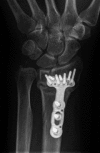

Background: A single volar locking plate (VLP) is now frequently used for open reduction and internal fixation (ORIF) of many types of distal radius fractures. Comminuted intra-articular distal radius fractures (AO C3-type) are typically the most challenging to surgically treat. No studies directly address the adequacy of a VLP alone for maintaining reduction of AO C-type fractures. We hypothesized that a single VLP provides an effective method for maintaining reduction for these fractures.

Methods: We retrospectively evaluated radiographs of a series of AO C-type fractures. Seventy-seven patients with 77 AO C3-type fractures were identified from billing records and were eligible for the study. All patients were treated by fellowship-trained hand surgeons. Radiographs at the time of union were compared to those from immediately postoperatively.

Results: Sixty-nine of 77 (89.6 %) fractures treated with VLP fixation alone for AO C3-type distal radius fractures united without loss of reduction. Eight of 77 (10.4 %) patients treated with VLP for AO C3 fractures lost reduction. The most common fracture fragment to lose reduction was the lunate fossa (5 of 8); loss of reduction of the scaphoid fossa die-punch fragment (2 of 8) and the radial styloid (1 of 8) were also seen.

Conclusions: The majority (89.6 %) of AO C3-type fractures treated with a single volar locking plate come to union without loss of reduction.